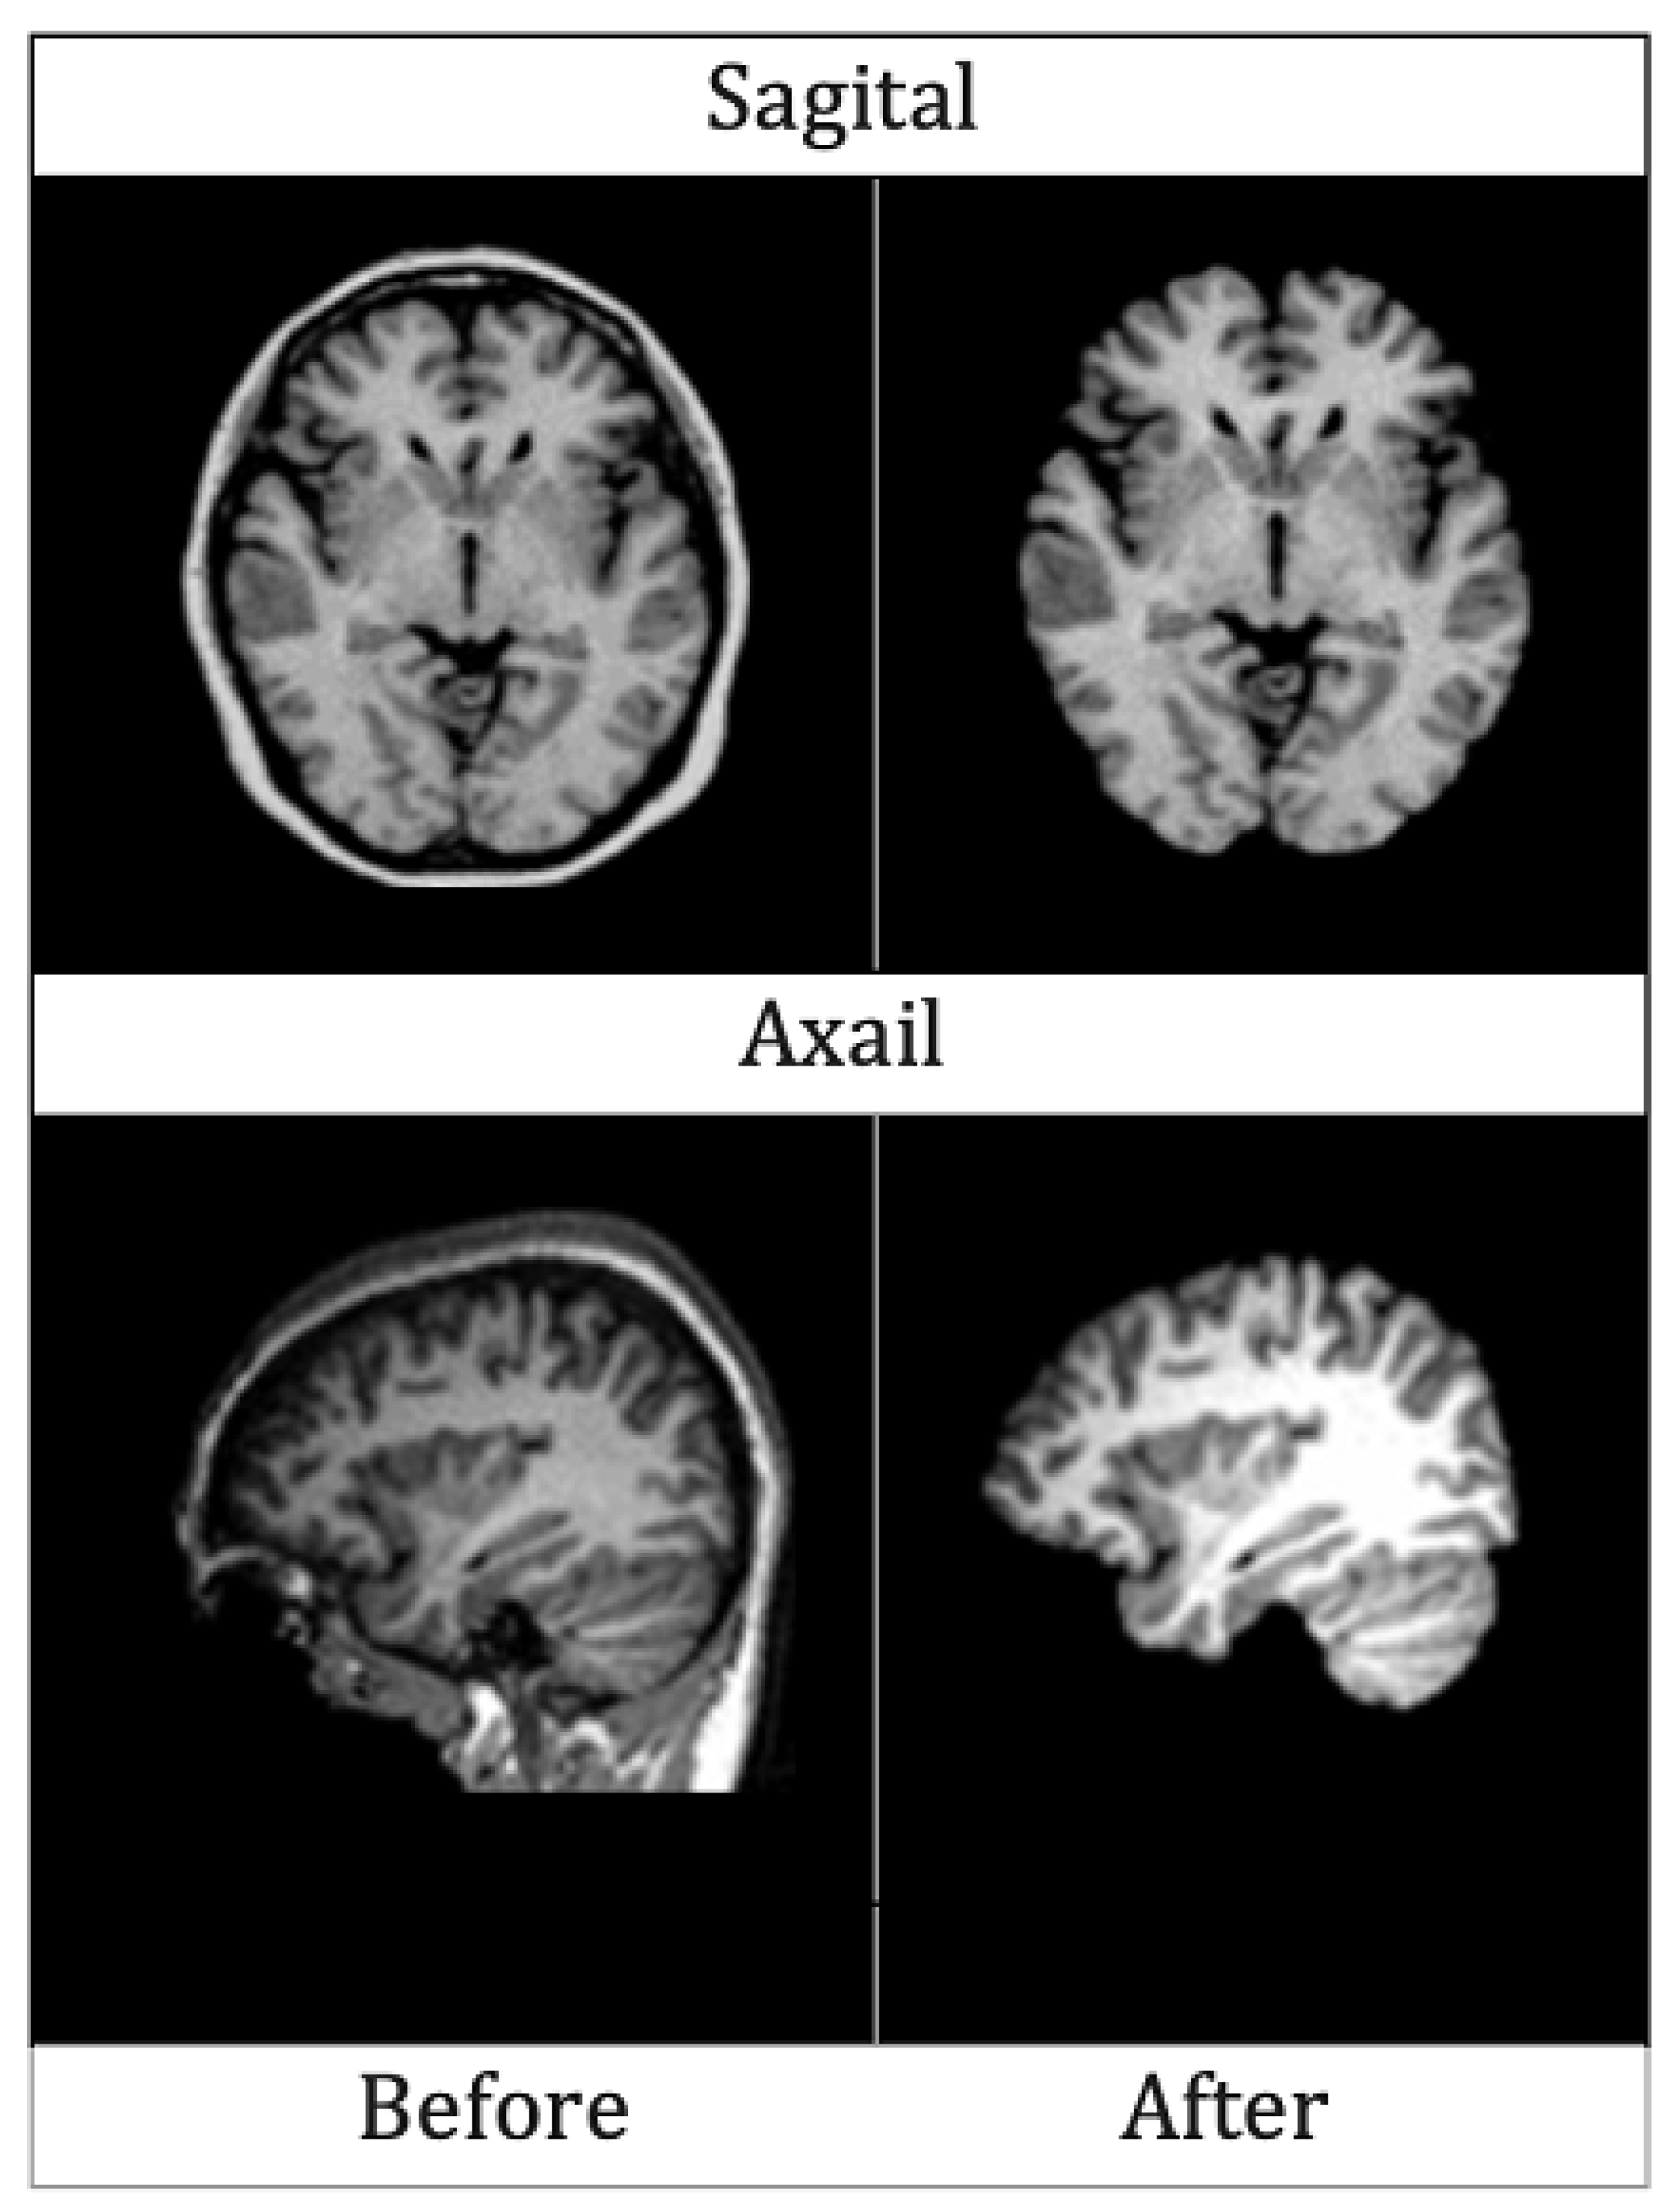

4.2.1. Skull Stripping

4.2.2. Segmentation

4.2.3. Normalization